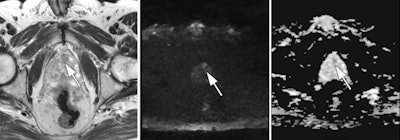

"A complete dependence on transrectal ultrasound-guided biopsy results can lead to improper disease-risk stratification and may jeopardize the opportunity for active treatment, with increased risk of disease progression and likelihood of metastasis," the team noted. "Multiparametric MRI and MRI-targeted biopsy are being increasingly utilized for the diagnosis of prostate cancer. They facilitate direct visualization and targeting of suspicious foci ... [and] MRI-targeted biopsies have been shown to enable higher detection of clinically significant cancers, enable more accurate tumor grading, and have complication rates comparable to those of transrectal ultrasound-guided biopsy."

Elfatairy's group conducted a study that included 40 men who underwent TRUS-guided biopsy, received results positive for prostate cancer, and then underwent multiparametric MRI before an in-bore MRI-guided biopsy between 2012 and 2016.

The team found that the overall cancer detection rate for MRI-guided biopsy was 65%. But MRI also found 14 previously unidentified cancers, 57.1% of which were clinically significant. The MRI biopsy led to upgraded disease severity in 40% of cases; only one case was downgraded to a lower Gleason score.